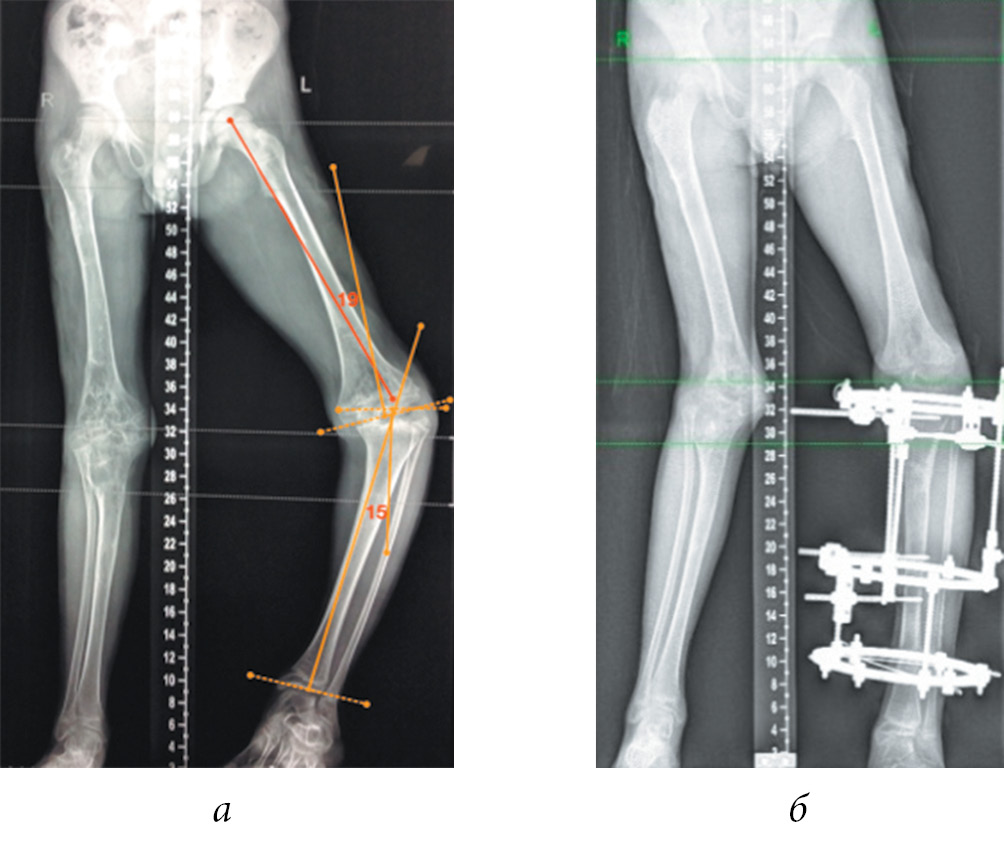

The shortening of the lower limb by 4 cm or more, the shoulder by 6 cm or more, and the forearm by 5 cm or more were considered an indication for surgical treatment, taking into account the age of the child. In the presence of angular deformities of the limb segments, accompanied by a shortening of 3 cm or more, one-stage correction of the length and shape of the limb segment by osteotomy was performed using compression-distraction osteosynthesis. At the final stage of treatment, to correct the multiplanar deformities of the bone metaphyses forming the knee and ankle joints, the Ortho-SUV reposition unit was used in three patients, which allowed to reduce the time and improve the quality of reposition (Fig. 1).

Fig. 1. Radiographs of patient G.’s lower extremities before (a) and during the correction of the shape and length of the right and left lower extremities using the Ortho-SUV reposition unit (b) and the standard layout of the Ilizarov apparatus (c)